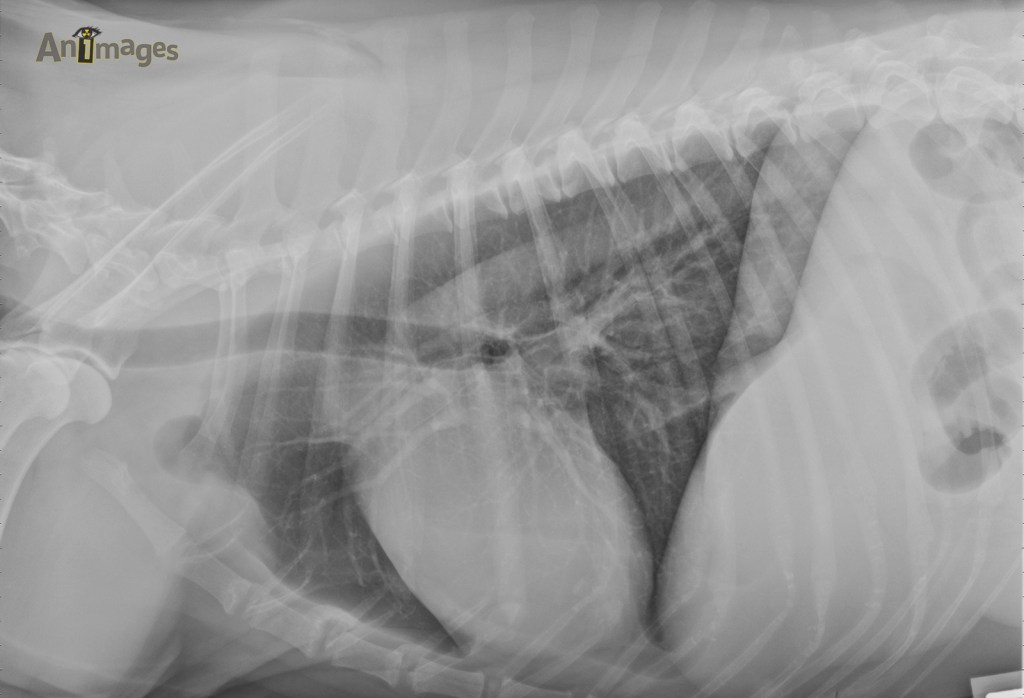

Lat G

Latérale gauche